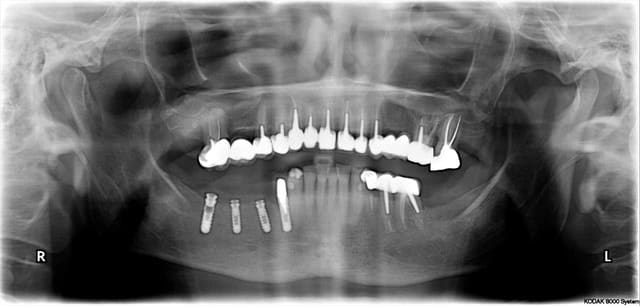

la première planif

grace à toi Béotien !

1 f9iy0w - Eugenol

2 dzt8ed - Eugenol

j'ai regardé ta première planif

photo 1:on voit bien les collisions, tu as juste 2,5mm entre tes 2 implants

mais tu aurais du garder l'intégralité des dents pour avoir les racines

photo 2:pour l'implant en 16 c'est très bien

photo 3:pour l'implant en 15 j'aurais mis un 12x4,1

Photo 4:On voit bien avec les collisions que comme cela tu as plus d'espace entre les implants (j'ai enlevé la collision du tien)